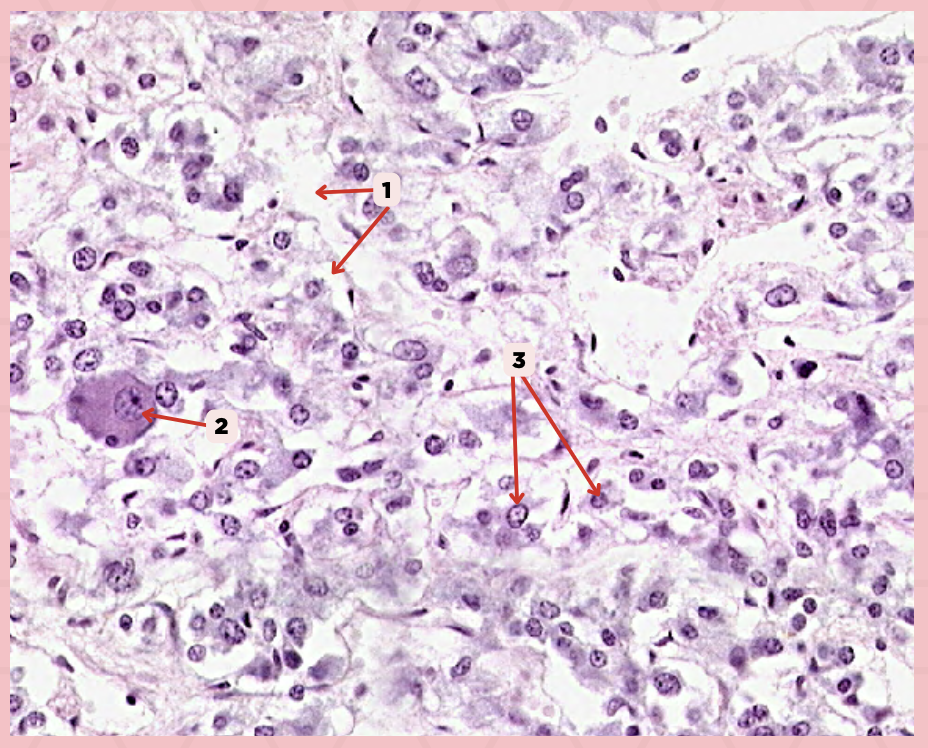

Pancreas

Identify the specimen.

Islets of Langerhans

Identify the structure labeled as 1.

Pancreatic Acini

Identify the structure labeled as 2.

Reticular Tissue

Identify the structure labeled as 3.

Beta-cells

Which cells occupy the central area of #1?

Pancreatic Acini

#3 delineates the pale- staining cells from the darker-staining cells. What do you call the darker-staining cells?

Pancreatic Duct

Identify the structure labeled as 1.

Reticular Tissue

Identify the structure labeled as 2.